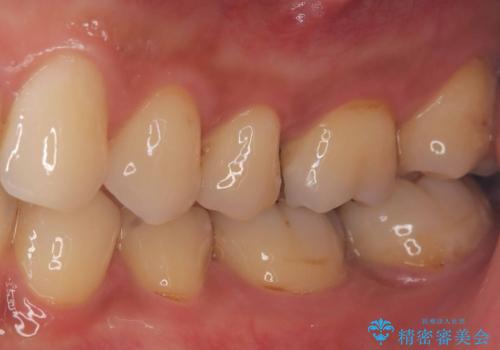

セラミックインレーで治療を行いました。

神経の近くまで虫歯が広がっていたため、虫歯の除去後、神経を保護する材料をおきセラミックインレーで治療を行いました。

保険適応の銀歯ではどうしても歯との適合が悪く隙間が出来てしまったり、材質の劣化により再び虫歯になってしまうケースがとても多いです。